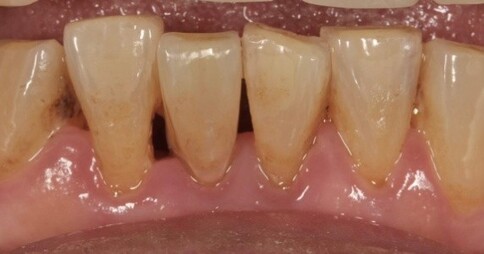

Case 2:下顎單顆假牙,齒質足夠支撐復型。